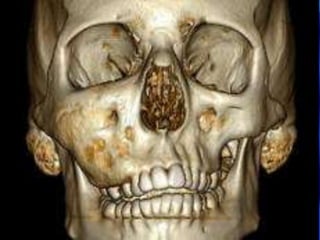

Fibrous Dysplasia

 Painless expansile dysplastic process of osteoprogenitor

connective tissue

 Maxilla most common

 Does not typically cross midline (one bone)

 Antrum obliterated, orbital floor involvement (globe

displacement)

 Radiology – ground-glass appearance

Fibrous Dysplasia  Painlessexpansile dysplastic process of osteoprogenitor connective tissue  Maxilla most common  Does not typically cross midline (one bone)  Antrum obliterated, orbital floor involvement (globe displacement)  Radiology – ground-glass appearance

• 89.